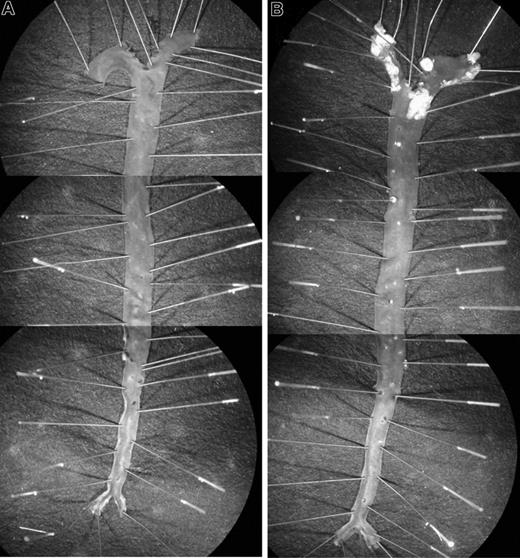

Littermates of various genotypes (apoE+/+HCII+/+, apoE−/−HCII+/+, apoE+/+HCII−/−, and apoE−/−HCII−/−) were fed a Western diet between the ages of 8 and 20 weeks and were then killed. Figure 1 shows typical images of pinned aortas obtained from apoE+/+HCII−/− and apoE−/−HCII−/− mice. Atherosclerotic lesions in apoE−/− mice were clearly demarcated from the surrounding normal intimal surface. No lesions were observed in apoE+/+ mice regardless of the HCII genotype. In the apoE-null background, however, atherosclerotic plaque areas were significantly greater in HCII−/− mice in comparison with HCII+/+ mice in the aortic arch (18.0% ± 4.7% vs 11.1% ± 3.0%, P = .001) but not in the thoracic aorta (4.4% ± 2.2% vs 2.8% ± 2.3%, P = .117) (Figure 2). Although the lesions in apoE−/−HCII+/+ and apoE−/−HCII−/− mice differed in total area, they were similar in gross appearance. No lesions were present in the abdominal aorta. Serum cholesterol, triglycerides, free fatty acids, and glucose were elevated in apoE-null mice as previously reported,21 but these parameters were unaffected by the HCII genotype (Table 2). In apoE+/+ mice, the HCII genotype did not affect the cholesterol, triglyceride, or glucose concentrations, but HCII−/− mice had approximately 30% lower levels of free fatty acids (P = .04).

Atherosclerotic lesions. Typical appearance of aortas from apoE+/+HCII−/− (A) and apoE−/−HCII−/− (B) mice. Mice were fed a Western diet beginning at 8 weeks of age and were killed at 20 weeks of age. To show the entire aorta in a single image, each panel is a composite of 3 adjacent microscopic fields. Atherosclerotic plaques are present in the aortic arch and to a lesser extent in the thoracic aorta of the apoE−/−HCII−/− mouse (B).